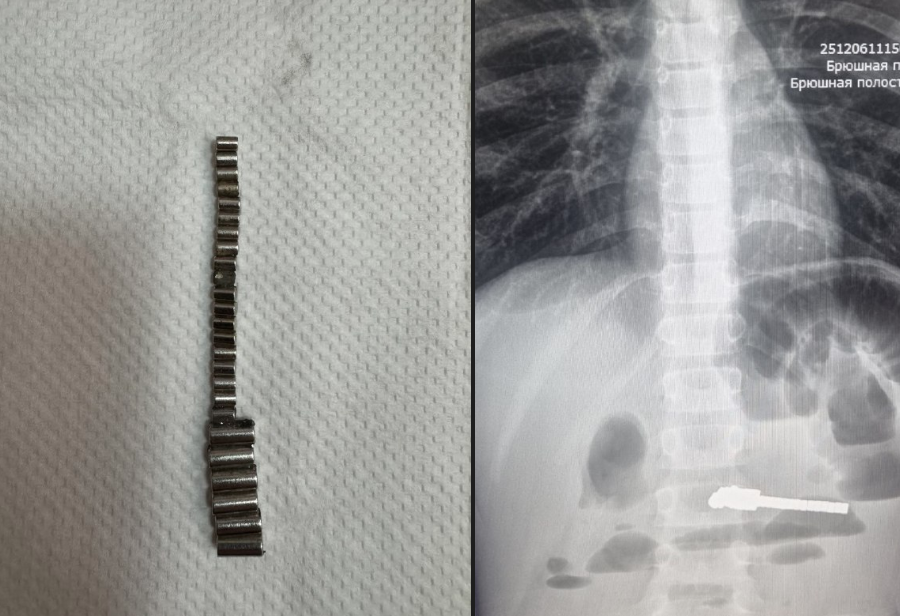

Непроходимость и некроз: 25 предметов извлекли из кишечника ребенка в Новосибирске

Фото: Минздрав НСО

Главный врач ДГКБ № 1 Евгения Аверкина поделилась историей спасения маленького пациента, поступившего в больницу с острой болью в животе и частой рвотой. Диагностика показала наличие множества посторонних тел в пищеварительном тракте, угрожавших жизни ребенка.

Хирургическое вмешательство потребовалось незамедлительно: медики диагностировали тяжелую форму кишечной непроходимости, вызванную притяжением магнитов друг к другу сквозь ткани организма. Операция оказалась успешной, врачам удалось удалить из тела ребенка 25 магнитов, предотвратив трагические последствия.